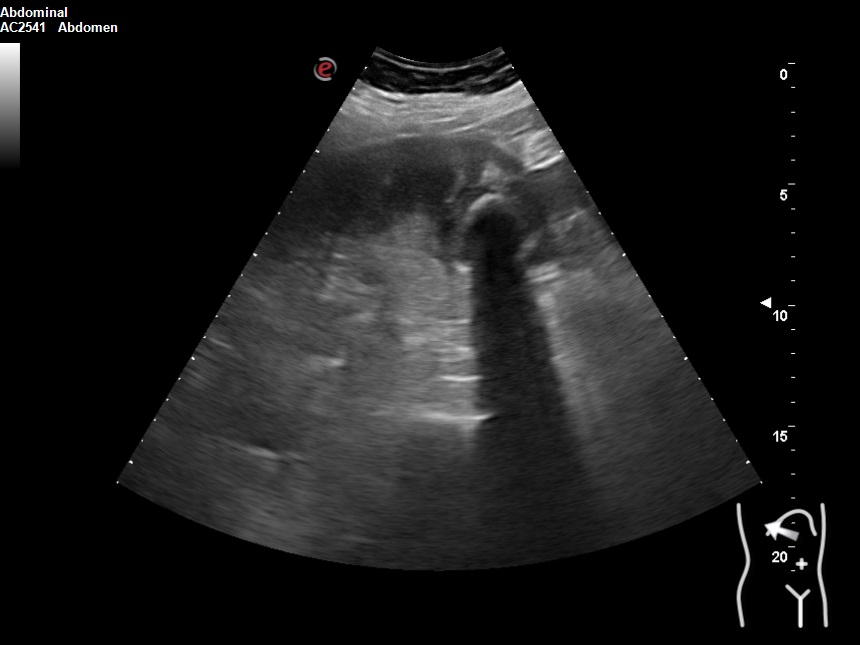

Hallazgos ecográficos

Vesícula biliar desestructurada, de paredes mal definidas con litiasis de 20 mm, que contacta con la pared de la segunda porción duodenal. Porta de tamaño normal. Vía biliar no dilatada.